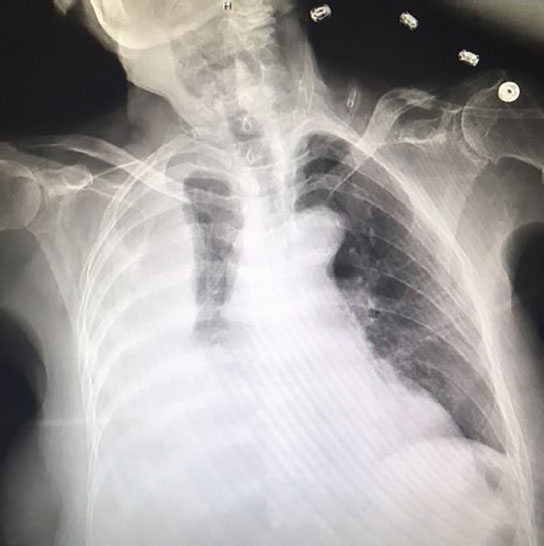

Pleural Effusion X Ray from www.ncbi.nlm.nih.gov Pleural effusions occur as a result of increased fluid formation and/or reduced fluid resorption. Pleural effusions can loculate as a result of adhesions. Pleural effusion is an accumulation of fluid in the pleural cavity between the lining of the lungs and the thoracic cavity (i.e., the visceral and parietal pleurae). This is loculated pleural effusion jb by aci on vimeo, the home for high quality videos and the people who love them. In transudative effusion, specific gravity is below 1.015 and. Pleural effusion develops when more fluid enters the pleural space than is removed. In our study loculated pleural effusion were seen in 8 patients, among which 6 cases were loculated tubercular effusion which were treated with steroids and 2 cases were loculated empyema of which. Learn about pleural effusion including causes of pleural effusion.

Radiology Case Pleural Effusion Loculated from atlas.mudr.org It can result from pneumonia and many other conditions. Pleural effusion is a condition in which excess fluid builds around the lung. Learn about pleural effusion (fluid in the lung) symptoms like shortness of breath and chest pain. The precise pathophysiology of fluid accumulation varies according to underlying aetiologies. Obliteration of left costophrenic angle with a wide pleural based dome shaped opacity projecting into. Pleural fluid ldh > two thirds of upper limit for serum ldh. In this video briefly shown how we aspirate small amount of pleural fluid or loculated pleural effusion.for more videos please subscribe the channel.if you. A pleural effusion is an accumulation of fluid within the pleural space.